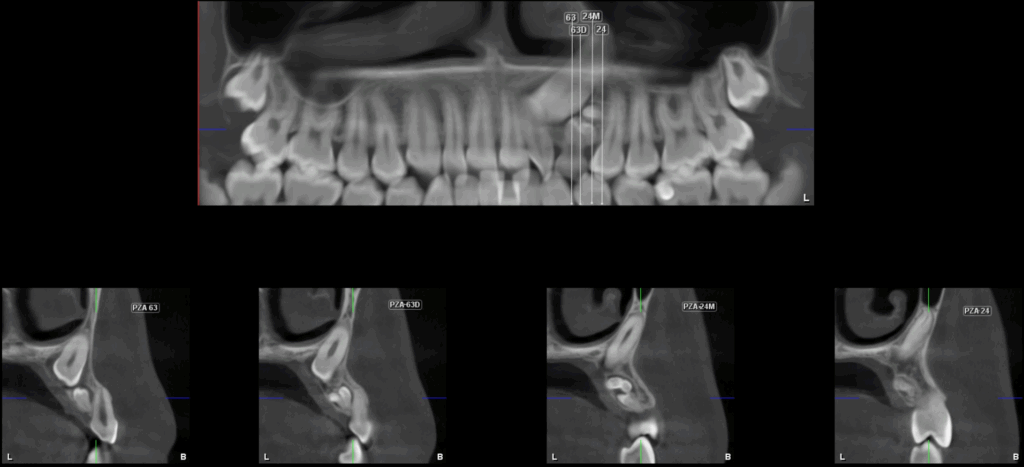

A la evaluación de la tomografía volumétrica (CBCT) en los cortes axiales (Figura 2) y transaxiales (Figura 3), se aprecia múltiples dentículos circunscrito de un halo hipodenso, localizada en palatino del tercio apical y medio de pieza 63, que ocasiona el desplazamiento de la pieza 23 hacia cefálico y adelgazamiento de la tabla ósea palatina.

CORTES TRANSAXIALES